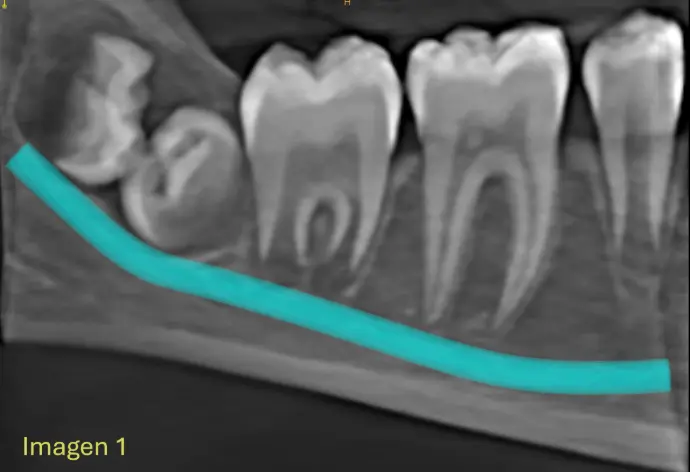

​Se Observa en la Cone Beam la formación dentro de un mismo saco coronario la formación de dos estructuras coronarias, correspondiendo a Pd 48 y Pd 49 (4to molar) Ambas piezas en proceso de formcion, completamente incluida, en intimo contacto con el conducto dentario inferior derecho sin signos de desplazamientos evidentes (IMG. 2), Ambas piezas dentarias se encuentran incluidas con la corona enfrentadas (IMG. 3),